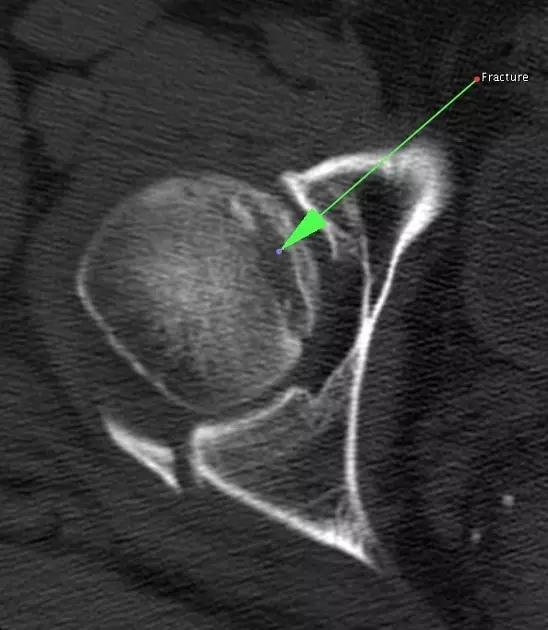

1. Hill-Sachs 损伤和反 Hill-Sachs 损伤

肩关节脱位时,肱骨头和关节盂发生撞击,肱骨头表面凹陷性骨折。

肩关节前脱位时发生的肱骨头后外侧凹陷性骨折,是经典的 Hill-Sachs 损伤(Hill-Sachs lesion);

-

而肩关节后脱位时发生的肱骨头前内侧凹陷性骨折,是反 Hill-Sachs 损伤(Reverse Hill-Sachs lesion/ McLaughlin lesion)。

Hill-Sachs 损伤的 CT 片 (来源:Hill-Sachs Injuries of the Shoulder)